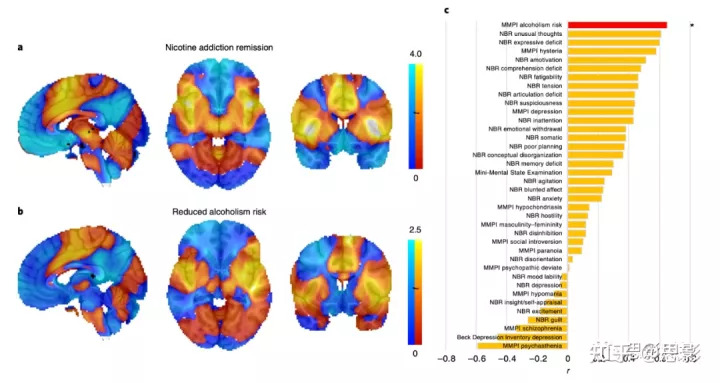

为了研究泛化,我们研究了 186 名完成酗酒风险评估的病变患者。与较低酗酒风险相关的病变与破坏吸烟成瘾的病变表现出相似的连接(图3a和b;空间r=0.65,置换检验P=0.04),即使控制吸烟状况(空间 r=0.69,置换检验 P=0.04)。数据集之间的这种一致性是由网络连接驱动的,而不仅仅是病变位置,因为使用传统 VLSM 重复分析未能显示相似性(空间 r=-0.15,P=0.83)。这种一致性也特定于成瘾风险,因为为其他 10 个明尼苏达多相人格量表(Minnesota Multiphasic Personality Inventory, MMPI)变量生成的地图以及成瘾风险地图(P<0.001)与使用其他神经心理学变量生成的 27 个地图不匹配(图 3c )。我们还确定了3例破坏尼古丁以外物质成瘾的病变病例报告,并发现网络连通性与破坏吸烟成瘾的病变相似(P<0.05;补充材料图 11)。

图3:吸烟成瘾缓解网络对酗酒的普遍性。

a,b,与吸烟成瘾缓解相关的病变的连通性特征(a)与降低酗酒风险相关的病变连通性特征(b)非常相似。地图以非阈值显示,便于直观比较。c,这种网络相似性特定于酗酒风险,因为为其他37个神经心理学变量生成的网络图与我们的成瘾缓解网络不匹配。NBR,neurobehavioral rating scale神经行为评定量表。r,映射空间相关系数与吸烟成瘾缓解图。*P < 0.05,未校正。